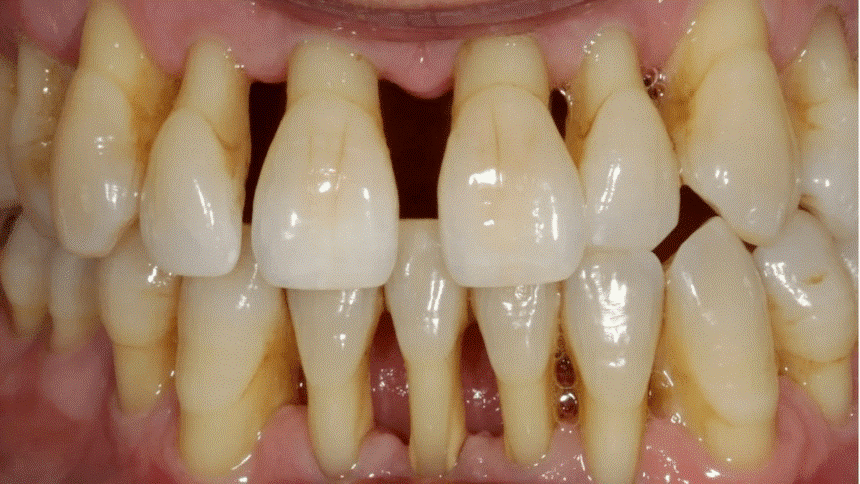

目前中老年人的牙齿疾病主要体现在四大方面:牙齿磨耗、牙龈萎缩、龋齿、牙周病。龋齿和牙周病可以说是中老年牙缺失的两大“元凶”。

(根面龋) (牙周病)